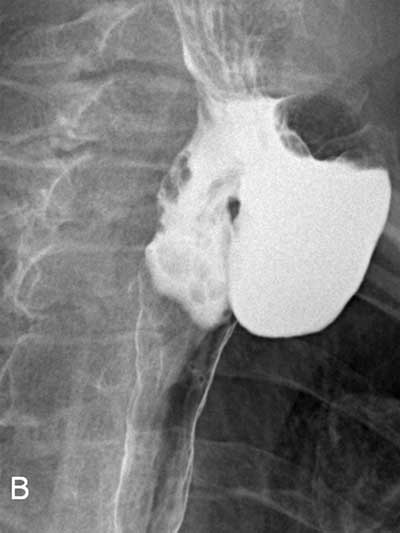

Figure B

Radiological right anterolateral view after barium administration.